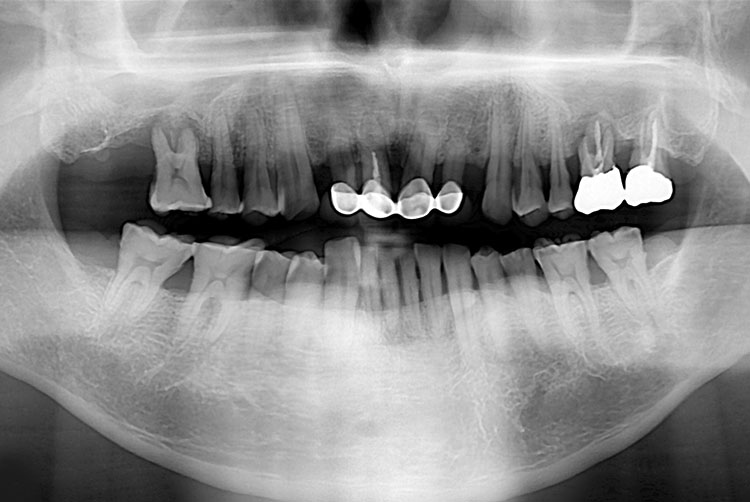

[임플란트] 임플란트

PX20221115_112315_8084_03746570.jpg

치료후 : 2022-11-15

세종치과는 많은 환자와 다양한 케이스를 바탕으로 항상 편안한 임플란트 수술을 제공하고자 노력하고,

오래동안 튼튼히 쓸 수 있는 임플란트 수술을 가장 큰 목표로 삼고 있습니다.